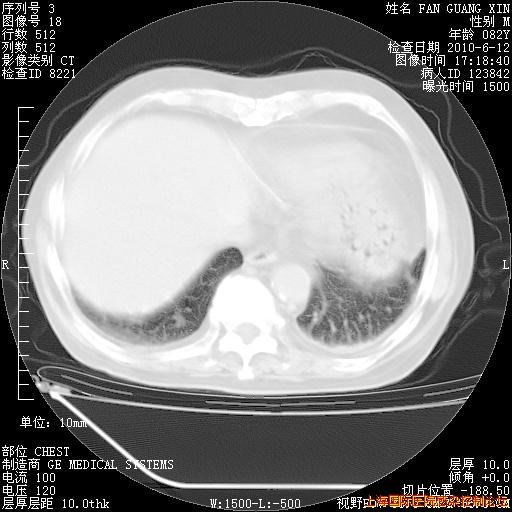

补发6月12日肺部CT肺窗

6月12日肺窗

整整相隔30天的肺部CT好像有所好转啊。甲强龙减量第3天,需要观察体温。

海管,自昨日你和我通完话后,不知您岳父消化道症状有无缓解?体温怎样?阅读7.12日胸部ct,个人认为目前激素治疗是有效的,甲强龙减量是适宜的。因在抗痨治疗,需密切观察肝功、肾功能和血常规。不过,老年、长期住院和大量使用激素,很担心菌群失调发生